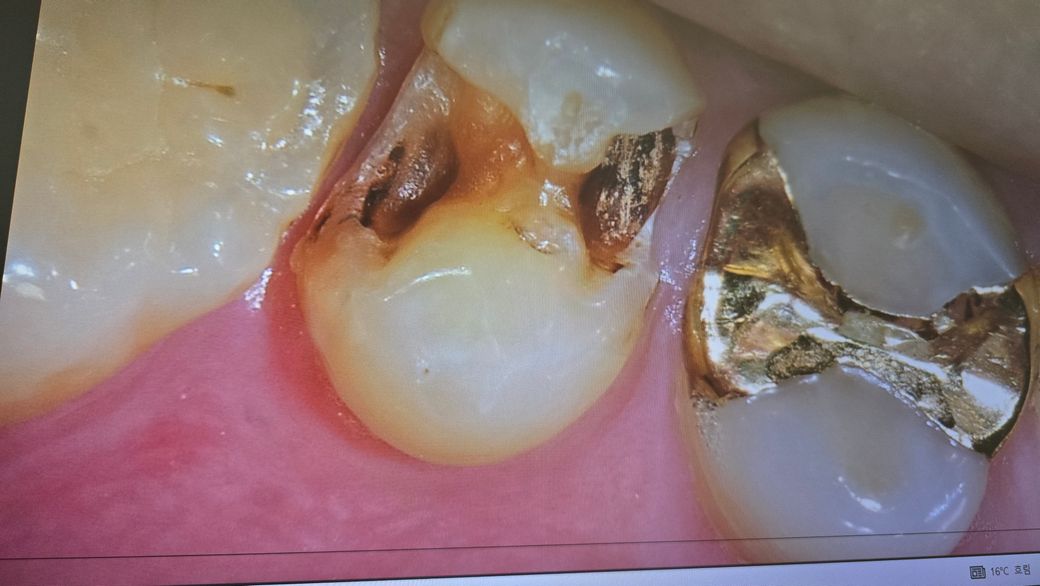

금 보철 제거한 사진인데 상태 좀 봐주세요

윗쪽 어금니인데 금 보철이 떨어져서 다시 붙였습니다

떨어진 상태에서 찍은건데 상태가 어떤지, 충치가 있는것인지, 추가로 보철 제거하고 치료를 받아야하는지 궁금합니다.

해당 부분이 단순히 변색인지 상한 건지 직접 체크해봐야 하며 썩었다면 새로 보철치료를 해야합니다.

사진으로 봤을 경우에는 어둡게 보이는 부분이 충치일 가능성이 높습니다.

치아에 충치가 있는 경우 충치를 제거하게 되면 원래 있던 보철물과 잘 맞지 않을 수 있는데 이런 경우에는 추가적인 보철치료가 필요할 수 있습니다. 자세한 확인을 위해서 치과에서 진료를 받아보는 것을 권유 드립니다.

아무래도 금 인레이 보철을 한 지 오래되었다면 내부는 충치도 생길 수 있고 보철물 접착제가 산화, 부식된 것도 있습니다. 충치의 경우 색상을 봐서는 급격하게 진행중인 충치는 아닐 가능성이 높을 것 같습니다.